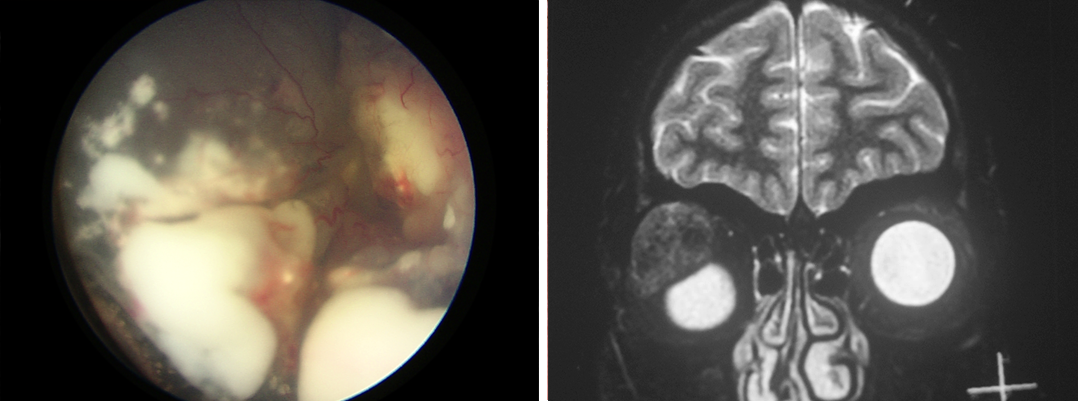

A premier one-day Continuous Medical Education (CME) program on the latest in ocular oncology returns for its 4th edition at LVPEI’s Kallam Anji Reddy Campus, Hyderabad.

With rapid advancements in diagnostics and treatment, staying ahead is crucial. EYECAN 2025 unites top experts for case-based learning, engaging discussions, and expert-led sessions to enhance clinical expertise.